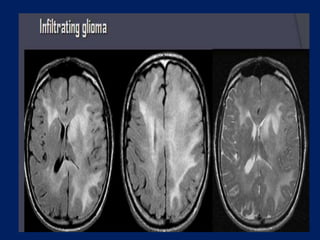

Diffuse astrocytoma